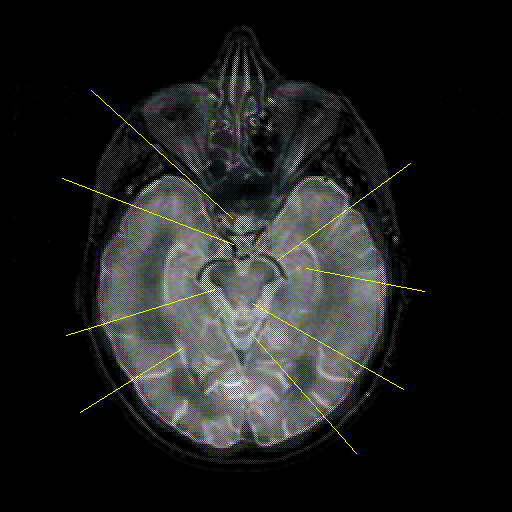

overlay : Slice 21

Slice 21

Unlabeled

Pointers

Labeled